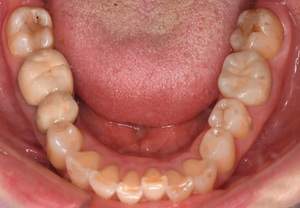

治療前

治療後

| 治療内容 | 右下6番・右上6番・左上6番フルメタルクラウン 除去、仮歯作成、 ジルコニアステイン形成、 右上6番・左上6番コア形成 |

| 治療費 | 合計 372,900円(2022年10月現在) ジルコニアステイン 110,000円×3本 仮歯 3,300円×3本 ファイバーコア 16,500円×2本 |

| 治療期間 | 3ヶ月 |

| 治療のリスク・副作用 | 仮歯の期間は仮歯が取れやすくなっている。 天然歯より硬いので噛み合う歯が欠けてしまうことがある。 |

| 特記事項 | 右上6番、左上6番に関しては根管治療が必要になる。 |